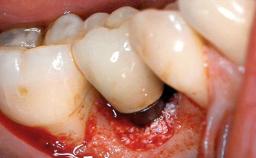

Oral implants are highly successful and offer long-term benefits, especially in the rehabilitation of edentulous patients or patients with oral defects following ablative tumor surgery (Albrektsson and coworkers 1986), and also after radiation therapy (Schiegnitz and coworkers 2014). With the number of implants placed globally going into the millions, implant dentists have observed some rare adverse events. Although carcinogenesis around implants is an exceedingly rare phenomenon, we recently reported about 15 patients treated for carcinomas adjacent to implants at our clinical department over a period of fifteen years (Moergel and coworkers 2014). The following case represents a patient of this cohort; it discusses possible risk factors and makes suggestions for a recall schedule. A 70-year-old woman was referred to our outpatient department for evaluation of a rapidly growing macroscopic alteration of the mucosa in the left mandible.